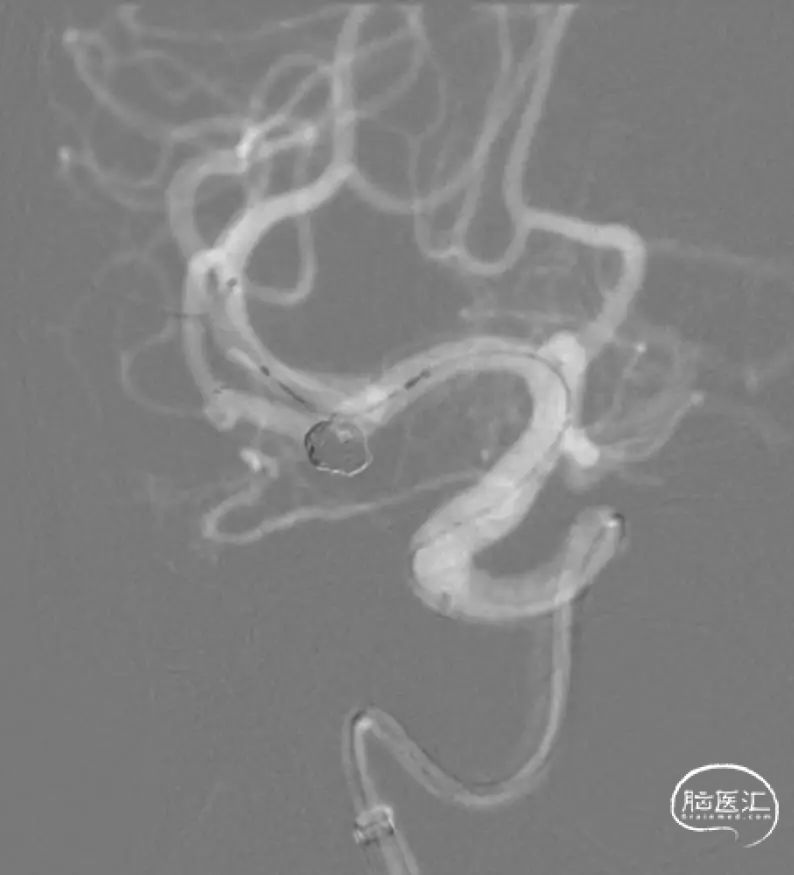

释放支架。

支架整个打开过程还是相当丝滑的。

SL-10穿网眼到达另一分支,备用。

弹簧圈栓塞。

造影分支血管良好。